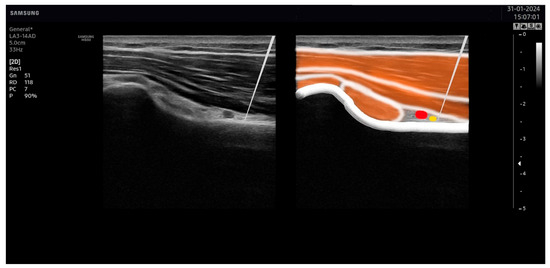

2.5. Ultrasound-Guided Percutaneous Nerve Stimulation

2.6. Placebo Ultrasound-Guided Percutaneous Nerve Stimulation